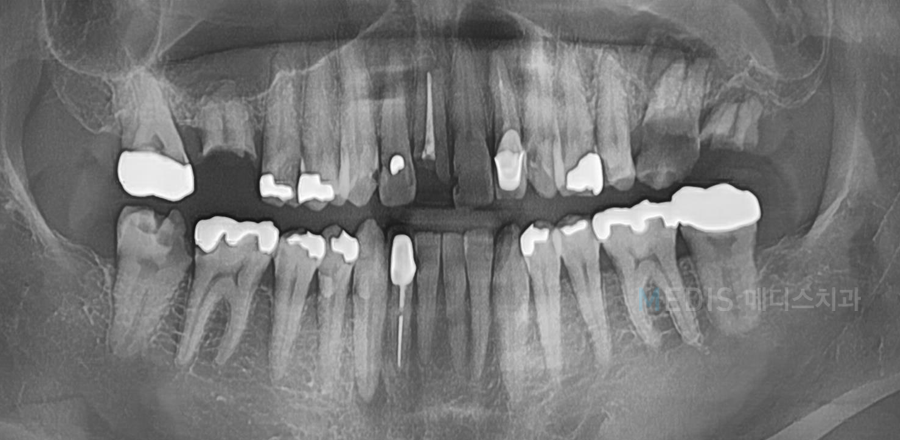

[디지털보철] 심한 치아우식 일반치료 및 임플란트 치료 후기

충치치료 + 임플란트 치료 전

※ 치료기간 : 2018.06.23~2018.12.22

(치료기간은 환자분의 협조도에 따라 달라질 수 있습니다)

※ 부작용 : 환자의 경향에 따라 통증, 부종과 멍 등의 부작용이 생길 수 있습니다.

* 상기 사진은 본원에서 치료를 받은 분의 동의를 얻은 사진으로 실제와 차이가 있을 수 있습니다.